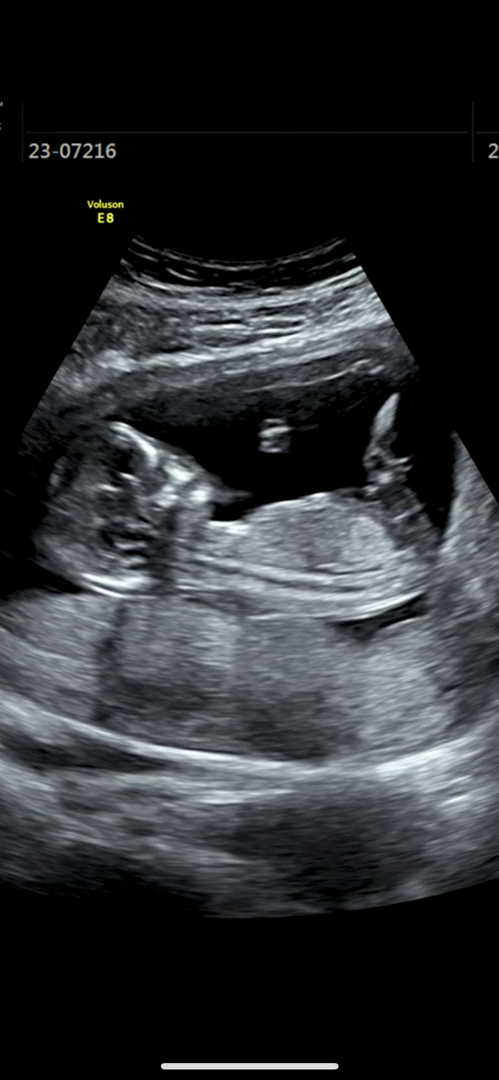

13주 각도법 고수님 계시나요🎀🌶️

오늘 아기가 등 돌리고 잘 안보여줬는데 ㅜㅜ 혹시 요로케라도 알 슈 있을까요? 전 아무리 봐도 모르겠어요,, 현재 13주1일입니당

아들각도같아요!